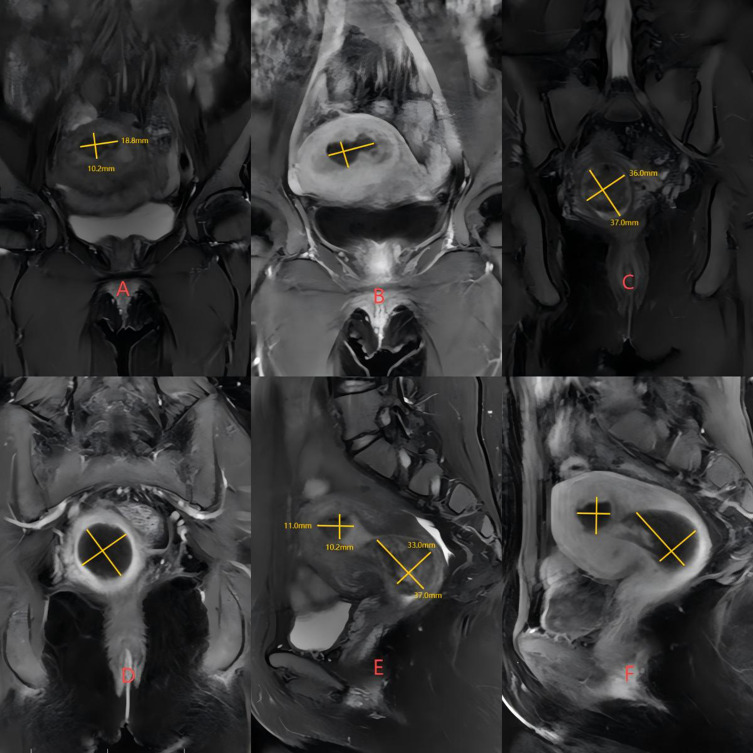

宫腔镜子宫肌瘤切除术是有生育需求的妇女切除粘膜下肌瘤的一线治疗方法。然而,面对大直径的2型粘膜下肌瘤,患者在宫腔镜检查时出现子宫穿孔、液体超载等并发症的风险更大。当2型粘膜下肌瘤直径大于4cm时,采用高强度聚焦超声(HIFU)、药物、宫腔镜三期治疗是有效且安全的。我们报告了一例30岁的未怀孕女性,她有子宫粘膜下肌瘤病史4年多,以月经量大、月经延长和继发严重贫血为主要症状。患者最初的盆腔磁共振结果提示2型子宫黏膜下肌瘤,直径大于4cm。我们首先对患者行HIFU,随后患者口服米非司酮片3个月,在宫腔镜手术前将患者的肌瘤类型转为0型,最终成功完成宫腔镜子宫肌瘤切除术(HM)。最后,我们得出结论,当2型粘膜下肌瘤直径超过4cm时,术前应考虑应用HIFU联合药物治疗,以最大限度地缩小肌瘤,改善贫血、痛经等症状,减少宫腔镜手术所需时间,提高手术安全性。

Hysteroscopic myomectomy is the first-line treatment for the removal of submucosal myoma in women facing fertility requirements. However, in the face of large diameter type 2 submucosal myoma, patients are at greater risk of complications such as uterine perforation and fluid overload during hysteroscopy. When the diameter of type 2 submucous myoma is greater than 4cm, the three-phase treatment of high intensity focused ultrasound (HIFU), drugs and hysteroscopy is effective and safe. We shared a case of a 30-year-old non-pregnant woman, who had a history of uterine submucous myoma for more than 4 years with symptoms of heavy menstruation, prolonged menstruation and secondary severe anemia. The patient's initial pelvic magnetic resonance results suggested a type 2 uterine submucous myoma with a diameter of more than 4cm. We first performed HIFU on the patient, followed by the patient's oral intake of mifepristone tablets for 3 months, and prior to hysteroscopic surgery, the patient's fibroid type was shifted to type 0, and finally successfully completed hysteroscopic myomectomy (HM). Finally, we conclude that when the diameter of type 2 submucosal myoma exceeds 4 cm, preoperative application of HIFU combined with drug treatment should be considered to maximize the reduction of fibroids, improve symptoms such as anemia and dysmenorrhea, reduce the time required for hysteroscopic surgery, and improve the safety of surgery.